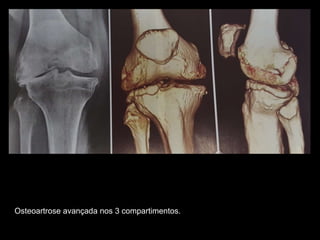

Osteoartrose avançada nos 3 compartimentos.

A) Radiografia anteroposterior com sustentação de peso do joelho de uma mulher de 58

anos. Osteoartrose avançada do compartimento femorotibial medial, o que ocasionou

uma configuração varo da articulação.

B) Radiografia AP também com sustentação de peso em outro paciente. Envolvimento

do compartimento femorotibial lateral ocasionando configuração em valgo.